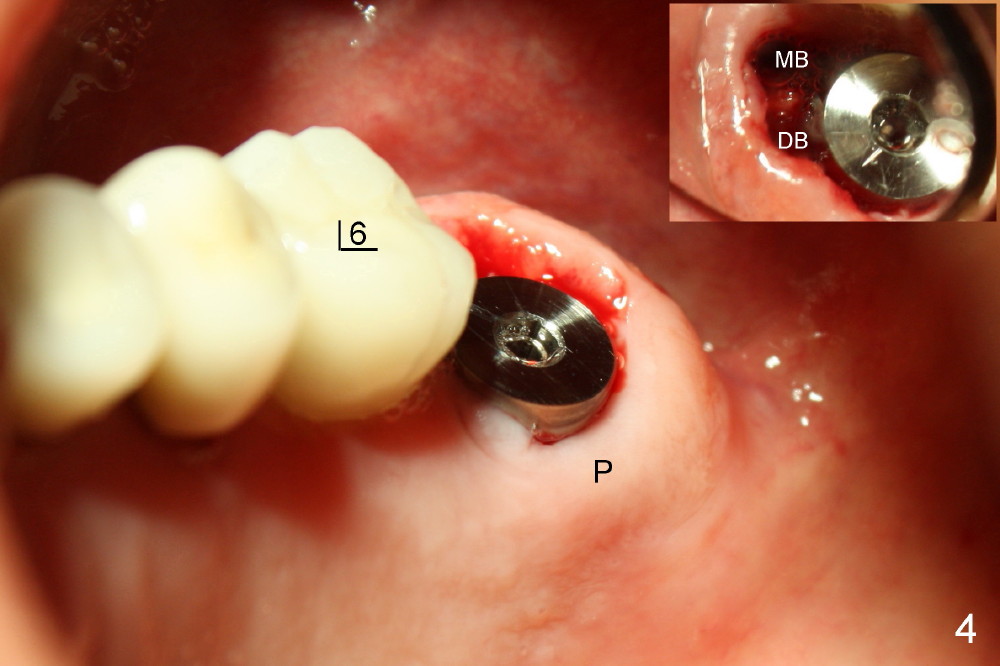

上颌磨牙有三个牙根,拔牙后一般有三个牙槽窝(图七(示意图)A:MB:近中颊侧;DB:远中颊侧;P:鄂侧),三个牙槽窝之间便是中隔(S)。如果中隔上面上颌窦不低,种植体应该种在中隔中。翁先生左上第二磨牙(图一:7)就与上颌窦无关,似乎后者不存在,前者牙根折裂,拔除后发现中隔鄂侧是一个斜坡,不容易插入圆骨凿或者钻头,所以用扁骨凿(图二)将中隔沿颊鄂侧劈开(图三),然后容易在中隔当中插入圆骨凿(图三插图白圆圈;图七B:蓝圆圈),由于中隔鄂侧阻力小,最后植牙(图七C:粉红色圆圈)不由自主地掉入鄂侧(图四),不得不移动颊侧粘骨膜瓣(图五B)关闭颊侧牙槽窝(图四插图(镜影观):MB;DB),图六镜影观(术后七天)显示种植体明显偏向鄂侧(P),可能造成以后修复困难。